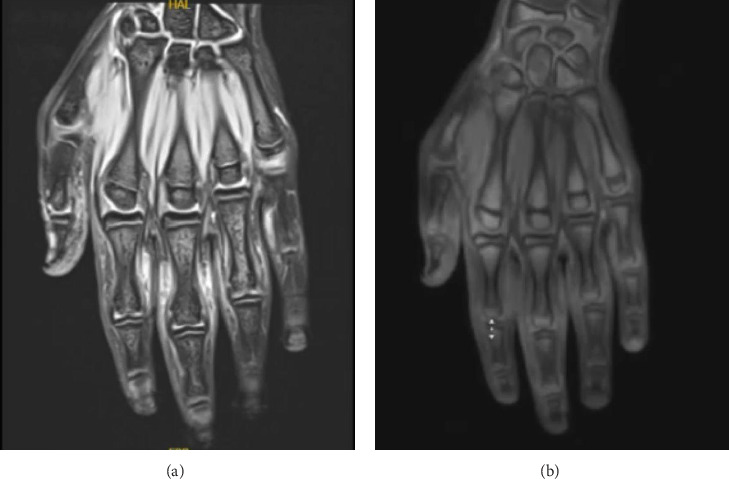

Pachydermodactyly (PDD) is a rare, underdiagnosed benign condition characterized by asymmetrical, bilateral fusiform swellings of the hands' proximal interphalangeal (PIP) joints. In this type of digital fibromatosis, cutaneous thickening is thought to occur due to repetitive mechanical irritation. Furthermore, due to its striking clinical appearance, PDD is commonly overlooked or misdiagnosed as other inflammatory arthropathies or pachydermoperiostosis. In addition, because of its elusive nature and resemblance to more serious conditions, clinicians should be aware of this condition. Herein, we present a case of PDD and discuss the differential diagnoses to improve recognition and prevent misdiagnosis.